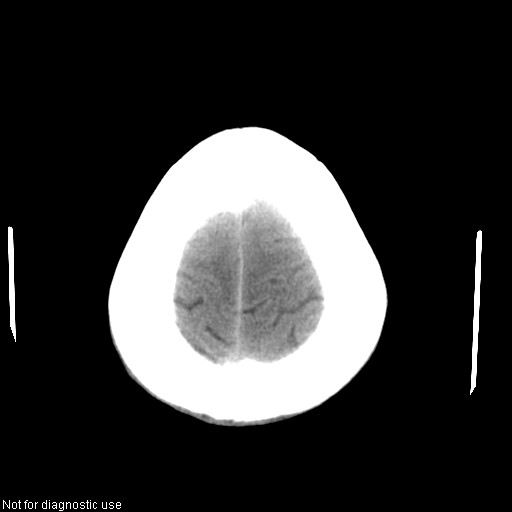

以下是引用hhcckk在2008-1-26 16:03:00的发言:[br]考虑病毒感染可能性大[br]1、病人发病时间短,1周,转移病灶时间长[br]2、楼主虽然没有告诉我们年龄,但从颅内情况来看,病人年纪不会很大,脑池,脑沟不是很明显,当然,可能有脑肿胀的原因,转移灶病人年纪一般较大[br]3、从病灶特点来看,转移多发生在灰白质交界区,多有指状水肿,占位效应明显,此病人呈对称性发布,发生在脑实质深部,与转移有所区别[br]4、病人经抗炎,止咳效果不好,可能是病毒感染,抗生素治疗效果不好[br]5、建议楼主1、增强 2、有呼吸系统的症状何不拍个胸片